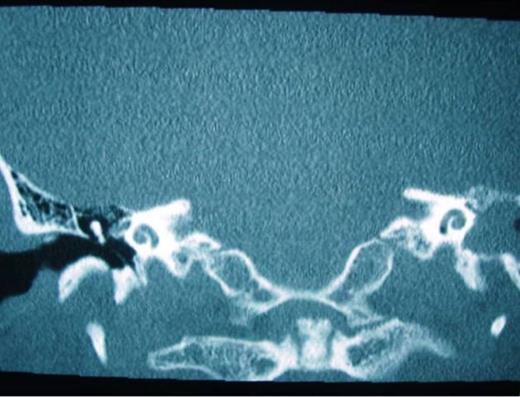

A 52 –year-old male with bilateral deafness and right facial nerve palsy presented to our clinic. The patient who was referred for consideration of cochlear implantation had a history of head injury 8 months before. An initial CT scan 2 months following his injury showed a transverse temporal bone fracture on the right side and a longitudinal one on the left side. Both cochleas appeared to be patent (Fig. 1, 2). The left ear was chosen for implantation as the injury was less severe on that side.

Right transverse fracture (black arrow) and left longitudinal fracture (white arrow)